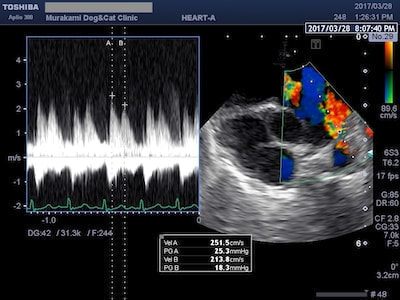

僧帽弁前尖収縮期前方運動(SAM)

HCMのなかには、僧帽弁前尖収縮期前方運動(SAM)と呼ばれる僧帽弁の異常な運動により、左心室から流出する血液の通路を妨害したり(左室流出路閉塞)、異常な弁の動きにより僧帽弁逆流を伴うものがあります。このようなHCMは閉塞性肥大型心筋症(HOCM)と呼ばれています。

SAMによる僧帽弁逆流

閉塞性肥大型心筋症(HOCM)は、SAMによる左室流出路閉塞と僧帽弁逆流を伴うため、左心房圧が上昇し肺水腫や血栓症のリスクが高まります。治療には血管を拡げて心臓の負担をとるための血管拡張薬や、尿を出して鬱血を改善するための利尿剤、血栓予防のお薬などを使います。

SAMによる左室流出路閉塞

異常な動きをする僧帽弁により左室流出路閉塞が起こると、左心室から流出する血流(大動脈血流)に高速血流が生じます(ホースの先端を摘むと水が勢いよく出るイメージ)。SAMの場合は左室流出血流波形がダガーシェイプ(ダガーナイフ型)になるのが特徴です。治療には左室流出路閉塞を緩和する目的で心拍数を抑えるお薬を使います。